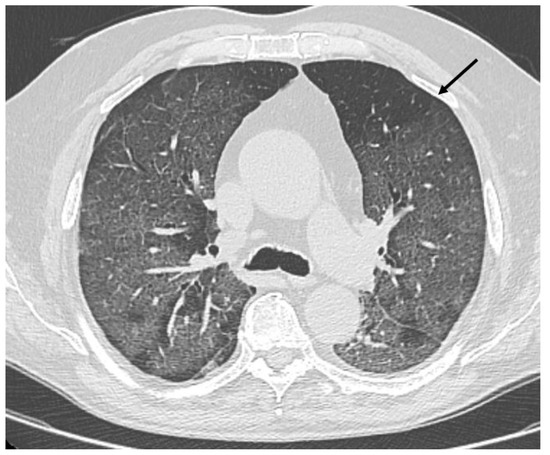

HRCT of the chest showed diffuse bilateral ground glass opacities (GGO) in all patients (Figure 1). Reticulation (Figure 2), traction bronchiectasis/bronchiolectasis (Figure 3), crazy paving and distortion (Figure 4) were observed in 29 patients (64%) at baseline. The total severity score was significantly higher at baseline in patients who eventually developed severe versus non-severe ARDS and pneumomediastinum/pneumothorax (16 versus 14; 95% CI 0.42 to 3.88; p = 0.01), as reported in Table 1. No other significant difference was observed at baseline.

Figure 1.

Diffuse bilateral ground glass opacities. Uneven distribution in the upper left lobe (arrow).